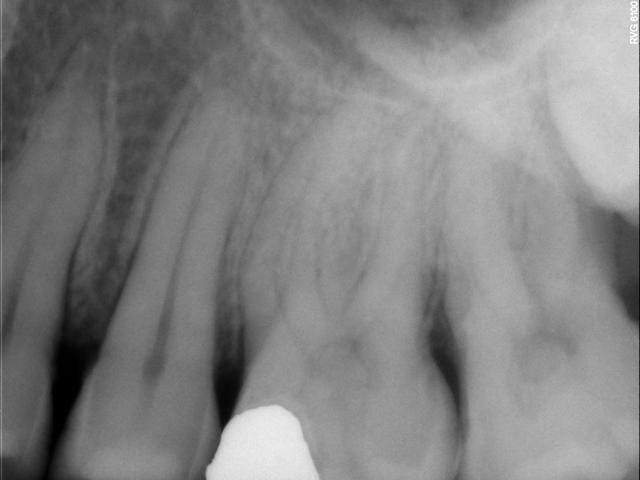

En pièce jointe la dent qui m'a fait posé cette question(radio pré-op) On se rapproche quand même bien du cas de Céramik, pour ne pas dire que c'est le même...

--